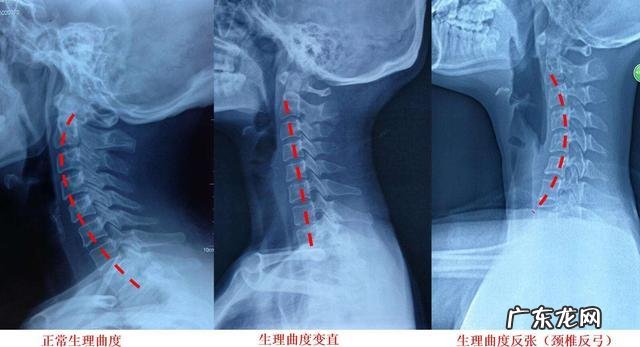

首先应该咨询医生是否需要进行颈部的x线或者是核磁检查,如果没有明显的神经卡压症状,比如上肢的麻木、刺痛的,进行颈椎的x线检查就够了,判断一下患者是否存在着颈型颈椎病,比如颈椎的曲度改变 。而如果出现了明显的麻木刺痛,甚至有手部的无力,应该进行颈椎的核磁检查 。出现颈椎疼醒的情况,很多患者都可能存在着严重的颈、肩、背部的筋膜炎改变,有些患者在查体的时候,我们甚至会在颈部与肩、背部肌肉止点的部位触及明显的肌肉锁头而改变这种情况,有些人称之为筋结,在西医我们称之为扳机点 。有时医生按压扳机点的时候,尤其是肩背部扳机点的时候,患者的疼痛会蔓延到上肢、甚至眼眶周围疼痛是非常剧烈的 。这主要是由于长时间的过度使用,肌肉、筋膜受到刺激,发生了撕裂之后又形成了炎症和瘢痕形成导致的,对于这种情况使用针灸、冲击波的zhi疗办法,以及手法医生的手法zhi疗,都会取得很好的zhi疗效果,经过zhi疗以后患者的症状就会有明显的改善,睡眠也会变得更加安稳 。有些问题比较严重的患者可以通过口服、外用药物以及局部封闭的办法来解决问题 。●有问题的患者,注意日常生活当中的一些细节也是非常有必要的 。